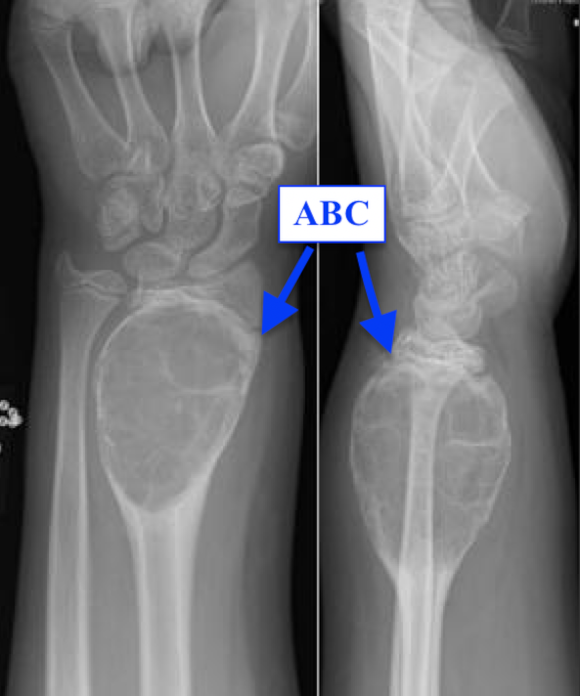

It is important to differentiate a UBC from an aneurysmal bone cyst (ABC). ABCs tend to be more expansive then UBCs. ABCs may be wider than the metaphysis and have multiple blood-filled cavities.

Plain radiograph is the imaging of choice and has high diagnostic accuracy. When a fracture has occurred a "fallen fragment" or "rising bubble" sign may be seen. CT and MRI are not usually necessary but can aid in eliminating other mimics of a unicameral bone cyst.